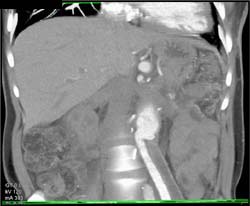

Celiac Artery Aneurysm